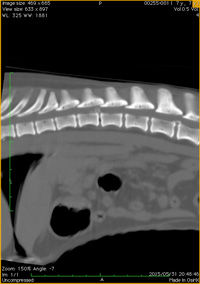

椎間板ヘルニア

(無麻酔撮影) -